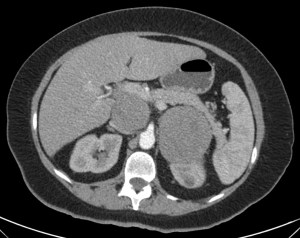

Paciente de 56 años en el que se descubre una masa suprarrenal derecha de 4,1 x 2.8 cm aprox., al realizar un TC de abdomen por otro motivo. Se procede al diagnóstico y caracterización de dicha lesión en la glándula suprarrenal derecha.

Lo ideal sería hacer un TC sin contraste y analizar las caracteríticas de la lesión. Si es una lesión homogénea, pequeña (<4 cm) y con contenido lipídico (<10 UH) los hallazgos son muy E para adenoma. En caso contrario, realizamos estudio con contraste (Vacío + Portal + Tardío a los 7-10 min), medimos la densidad con ROI y aplicamos las fórmula Washout.

En TC son lesiones inferiores a 3 cm, homogéneas, bien delimitadas y de baja atenuación por el contenido graso que lo componen. Con contraste, como dijimos anterioremente, captan y lavan rápidamente.